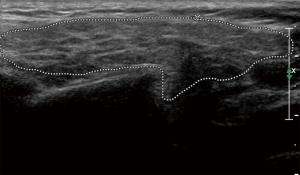

The principal ecostructural abnormalities detectable by SGUS are the following: parenchymal non-homogeneity, hypo-anechoic or hyperchoic areas (due respectively to cysts or calcifications), size variations, irregularities in glandular profiles and the presence of intra- or periglandular lymph nodes (19) (Figures 3-5). As highlighted by several authors (9,20), the most relevant SGUS alteration of pSS is the parenchymal inhomogeneity detectable bilaterally. This ultrasound finding, is the one that has shown the greatest agreement with the alterations documented with the scintigraphy of the salivary glands, sialography, and minor labial salivary gland biopsy (LSGB) (21,22). At the level of the parotid and submandibular glands, SGUS shows the best relationship of sensitivity to specificity, with a positive predictive value of 72.0% and a negative predictive value of 96.0% (23). Compared to contrast sialography and to salivary gland scintigraphy, SGUS showed higher sensitivity (75.3%, 72.7% and 70.1%, respectively), with similar specificity (83.5%, 84.9% and 82.3%, respectively) (7). Ultrasound findings of hypoechoic, multiple, circumscribed or confluent areas and/or multiple cysts correspond to a histological pattern of ductal ectasia surrounded by lymphocyte infiltrate or dilated glandular lobes surrounded by lymphocyte aggregates. In particular, Kawamura et al. (24) and Salaffi et al. (7,12) demonstrated that the anomalies documented at SGUS are strongly related to histological changes (12), and that the SGUS score proposed for classification is well correlated with sialographic classifications (12). Cornec et al. (15) have verified that morphological abnormalities of the salivary glands can be detected early in the course of pSS. The diagnostic characteristics of the SGUS also seem not to vary during the disease. Applying an ultrasound cut-off of 5, the proposed SGUS scoring system was slightly less specific (85.7% vs. 77.9%) but more sensitive (94.9% vs. 98.7%) compared to the AECG criteria (4,13).